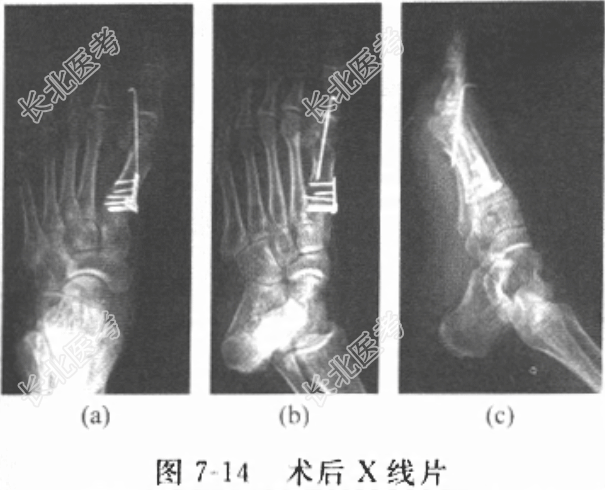

[材料题] 患者男性,46岁,以“发现左趾外翻畸形十余年,左足底疼痛半年”为主诉入院。十余年前发现左趾外翻畸形,无局部红肿疼痛,无皮肤破溃,无拇趾活动受限,当时未予重视,未予特殊处理,左趾外翻畸形渐加重,半年前出现左足底疼痛,行走后加剧,予镇痛对症治疗后无明显改善,求诊本院,门诊拟“左外翻畸形”收入住院。发病以来,患者精神可,饮食正常,大小便自解。既往体健,否认“心、肝、肺、脾、肾”等重要脏器疾病史,否认传染性疾病史,否认外伤史、输血史,否认食物、药物过敏史。体格检查:T37.1℃,P80次/分,R18次/分,BP110/70mmHg。神志清楚,对答切题,言语清晰,呼吸平稳,未闻及异常气味。胸腹部未见异常,无压痛。专科检查:脊柱生理弯曲存在,无畸形,各棘突无压痛、叩击痛,活动正常。左趾外翻畸形,外翻角度约40°,第一跖趾关节内侧肿大突出,表面皮肤稍红,局部压痛。左足底第2、第3跖骨头处可见胼胝,局部有压痛,趾活动稍受限,肢端血运好,左足皮肤感觉无改变。辅助检查:左足正位X线片(图7-13)示左外翻畸形。外翻角(HVA)30°,第1、第2跖骨间夹角IMA25°。 患者入院后检查三大常规、生化全套、凝血四项、心电图、胸部X线片等均提示未见明显异常。患者诊断明确,外翻畸形逐渐加重,左足底疼痛已半年,影响正常行走,予镇痛等对症治疗后无明显改善,患者本人手术愿望强烈。其左足正位X线提示左外翻畸形。外翻角(HVA)30°,第1、第2跖骨间夹角(IMA)25°,有绝对的手术指征。择期行第一跖骨截骨+Silver软组织手术,因该患者第1、第2跖骨间夹角较大,单纯Chevron截骨矫形不足,应联合跖骨基底截骨。跖骨头Chevron截骨后予克氏针固定,跖骨基底截骨后以微型钢板内固定。术后X线片如图7-14所示。